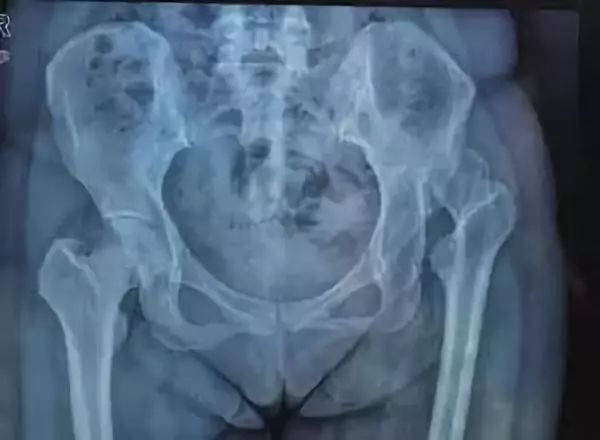

你的髋关节是一个球窝关节,可以想象成一个球跟一个碗,球在碗里可以各个方向良好活动,保证了关节的活动性!并提供能够承受身体重量所需的稳定性。

髋关节的“球”部分位于股骨或者叫大腿骨的顶部,而“窝”是骨盆中的一个碗,称为髋臼。

3、骨折

骨折是由于意外事故、跌倒或运动受伤而导致的身体上的骨折。其他原因可能是由于老年人骨质疏松症或者骨密度低下。这两者都导致骨质疏松。

髋部骨折包括股骨骨干骨折和骨盆骨折,老年人常见股骨颈骨折,致死率很高!

这些损伤后需要立即就医,骨头可以通过石膏模型、夹板或外科手术重新组合,手术使用钢板或螺钉固定骨折,从而使骨头愈合并重新长在一起。

5、缺血性坏死

这个可能大家就比较熟悉了,因为黑锅经常科普到!缺血性坏死主要发生在股骨头,当股骨头骨折或其他损伤中断股骨头血液供应时,非常容易发生。

它也可能由发育障碍(如先天性发育不良)和某些药物的使用引起,特别是激素类的药物(主要用于治疗哮喘、皮肤不适和肾脏病等)。

治疗过程可能很快见效,但症状也可能在几周或几年后再次出现。此病治疗的重点是通过药物和治疗预防进一步的股骨头骨质流失。

而在晚期病例中,通常需要外科手术,包括钻孔减压、骨移植、骨重塑和髋关节置换。